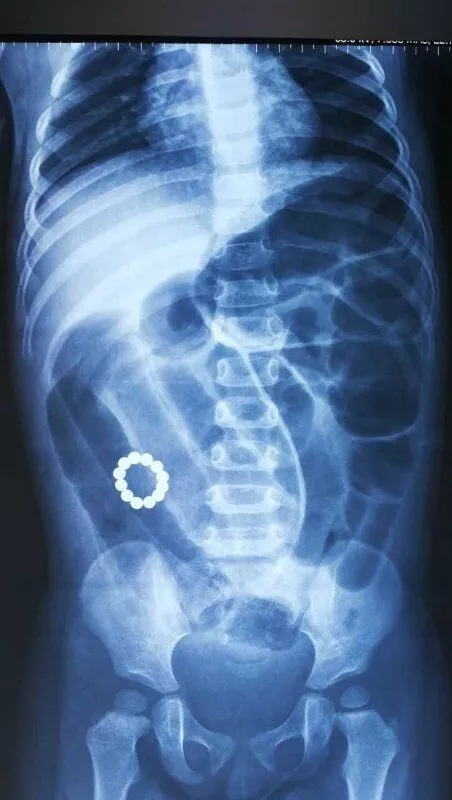

这名孩子同样是因为吃不下东西、呕吐,且精神差到医院急诊科就诊。医生经过检查,发现孩子的肠道里有一个圆环,像是12个小圆球串起来的。

看到这里,家长才想起,家里有十几个小吸铁石不见了。这些吸铁石到了孩子的肚子里后,首尾相连吸到了一起,还形成了一个圆环,让大家哭笑不得。